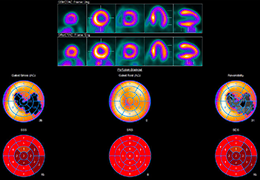

High-quality and fast 3D reconstruction and 3D rendering

Performs 3D reconstruction and volume rendering.

Side-by-side comparative assessment for pre- and post-operative scans.